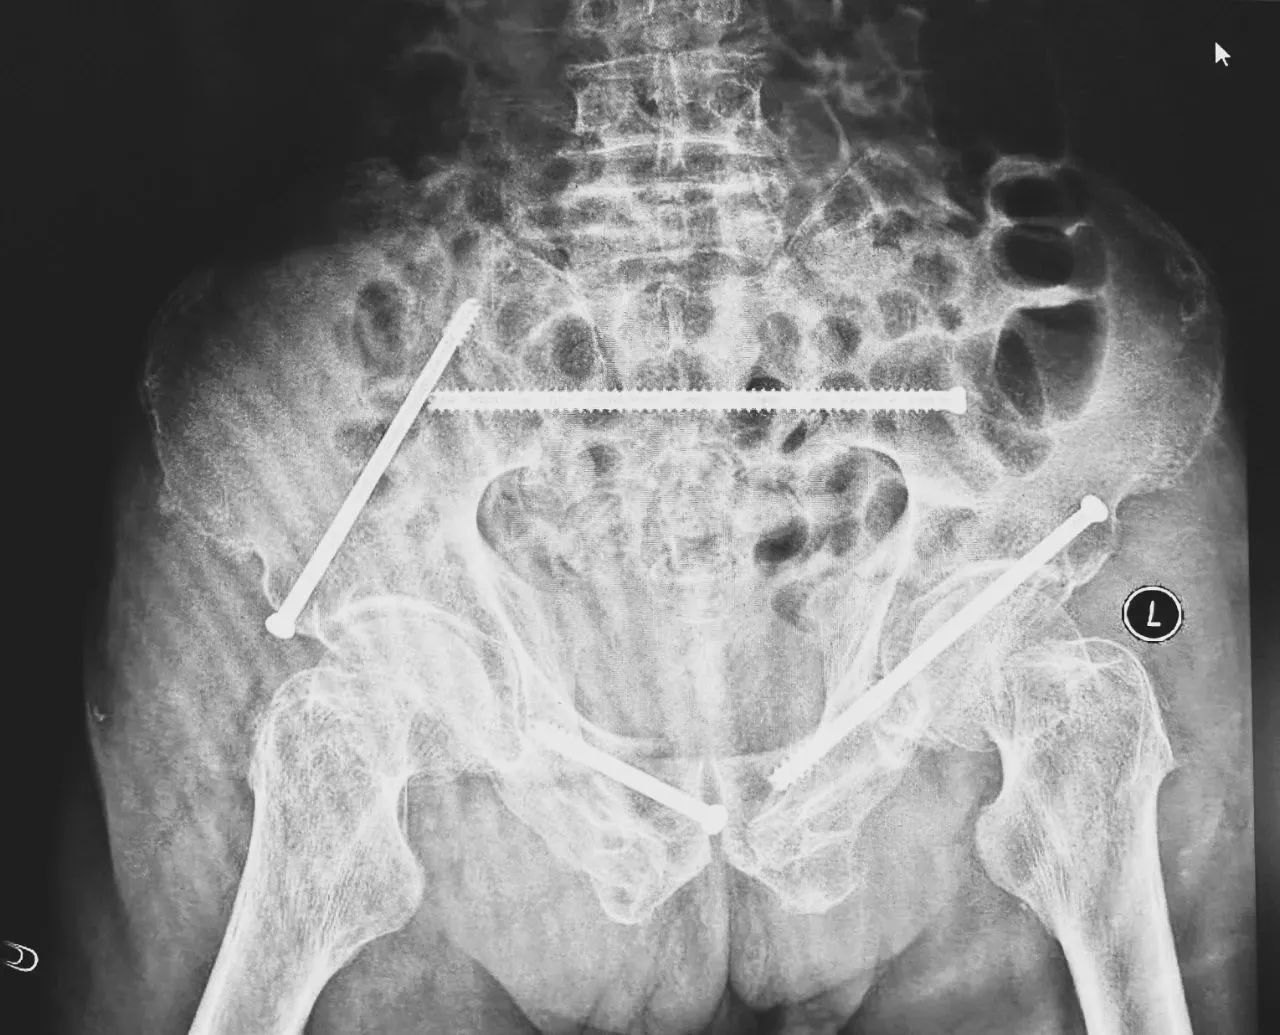

無影燈下,智能骨科團隊將患者示蹤器,放在左側(cè)髂前上棘,使用術(shù)中三維影像設(shè)備獲取骨盆的三維圖像,掃描結(jié)果傳輸至機器人導(dǎo)航系統(tǒng),完成螺釘置入的位置和走形,并在機器人的引導(dǎo)下分別置入4枚通道螺釘。置入后再次進行CT掃描驗證,證實導(dǎo)針精確置入。

在骨科手術(shù)機器人毫米級精度的引導(dǎo)下,這項原本高難度、高風(fēng)險的手術(shù)變得更加精準(zhǔn)高效。手術(shù)共計耗時1個半小時,術(shù)中出血不到20毫升,每枚螺釘置入位置的切口長度約1.5厘米,完美達(dá)到了預(yù)期。術(shù)后,王大爺安全返回病房。

術(shù)后第二天,醫(yī)生團隊復(fù)查X片顯示螺釘植入位置非常滿意,骨折基本達(dá)到穩(wěn)定復(fù)位,同時,復(fù)查的全血細(xì)胞計數(shù)中,血紅蛋白指數(shù)為102g/L。術(shù)后第三天,在智能骨科病房護理團隊及康復(fù)師的指導(dǎo)和護理下,王大爺可以坐立在床上。術(shù)后第四天,王大爺迎來了出院日,“得虧有了這么先進的醫(yī)療技術(shù),讓我還能下地行走,謝謝你們!”

螺釘植入位置非常滿意